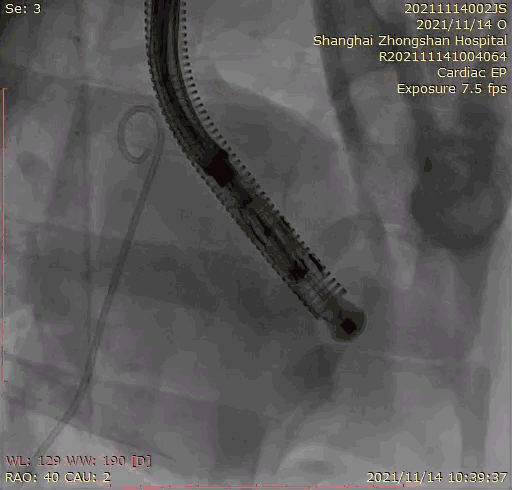

本次臨床前研究經(jīng)右側(cè)頸靜脈置入LuX-Valve Plus輸送系統(tǒng)可調(diào)彎鞘管,在DSA及超聲引導(dǎo)下將人工三尖瓣瓣膜植入到原有三尖瓣位置,利用獨(dú)特的錨定技術(shù)將人工瓣膜支架可靠固定在預(yù)定的位置。

上海中山醫(yī)院葛均波院士、錢菊英院長、周達(dá)新教授、潘文志教授、潘翠珍教授、李偉教授共同完成此次臨床前研究。術(shù)后葛均波院士對Lux-Valve Plus的器械操作性能給予了高度評價,DSA和超聲影像也顯示出在本次研究中Lux-Valve Plus的安全性和有效性俱佳。